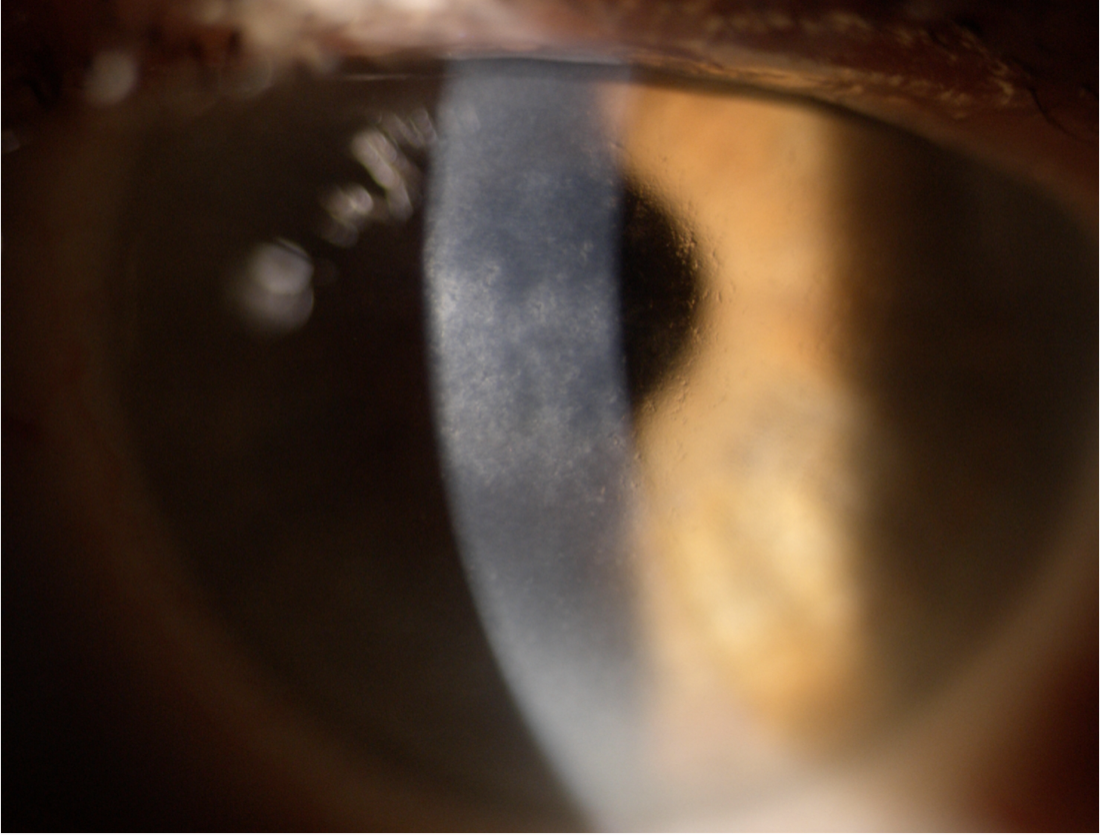

가장 전형적인 type 1 격자각막이상증은,

상염색체 우성으로 유전하여, 10세 이전에 발병하여,

양안의 각막 기질 표층부에 격자형의 가치진 모양의 선이 발생합니다.

그리고 소결정의 혼탁이 발생하면서, 점점 격자 형태가 갖추어집니다.

이러면서 이러한 각막 혼탁이 상피층 아래에 위치하기 때문에, 각막 상피의 진무름이 일직 발생합니다.

이후 40-50대에는 각막 혼탁으로 인한 심한 시력장애를 유발하게됩니다.

각막의 중심부를 주로 침범하며, 주변부는 침범하지 않는 것이 특징입니다.

처음에는 상피하 점모양의 혼탁으로 부터 시작하여,

점차 아밀로이드 물질이 침착하면서, 격자형태가 나타나는고 진무름이 반복됩니다.